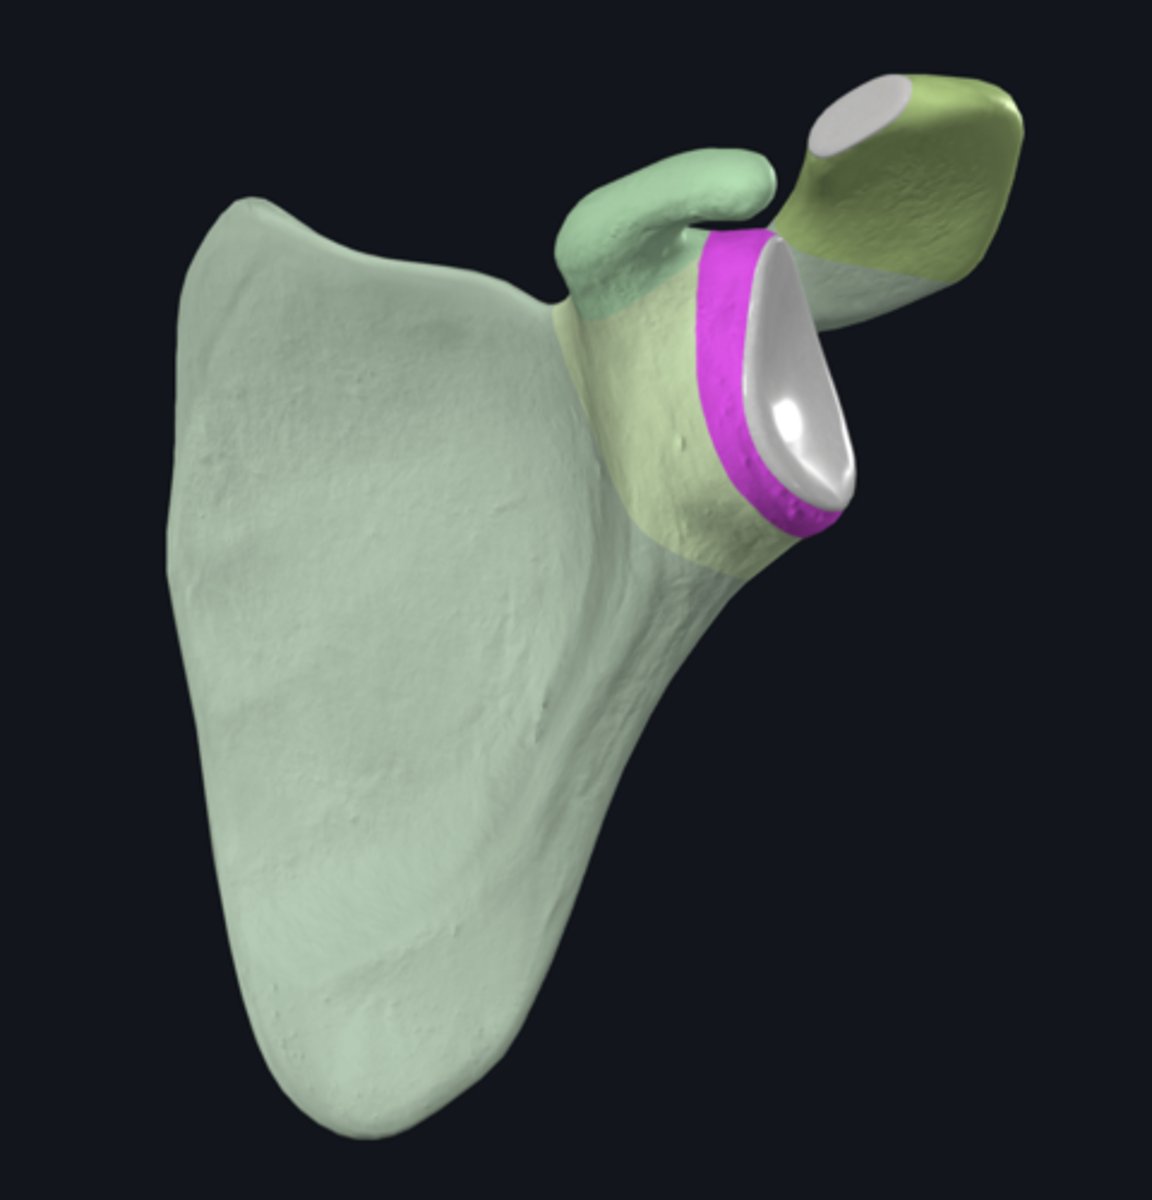

Acromion

Superior angle of scapula

Coracoid process

Head of scapula

neck of scapula

acromial angle

clavicular facet

glenoid fossa

infraglenoid tubercle

spine of scapula